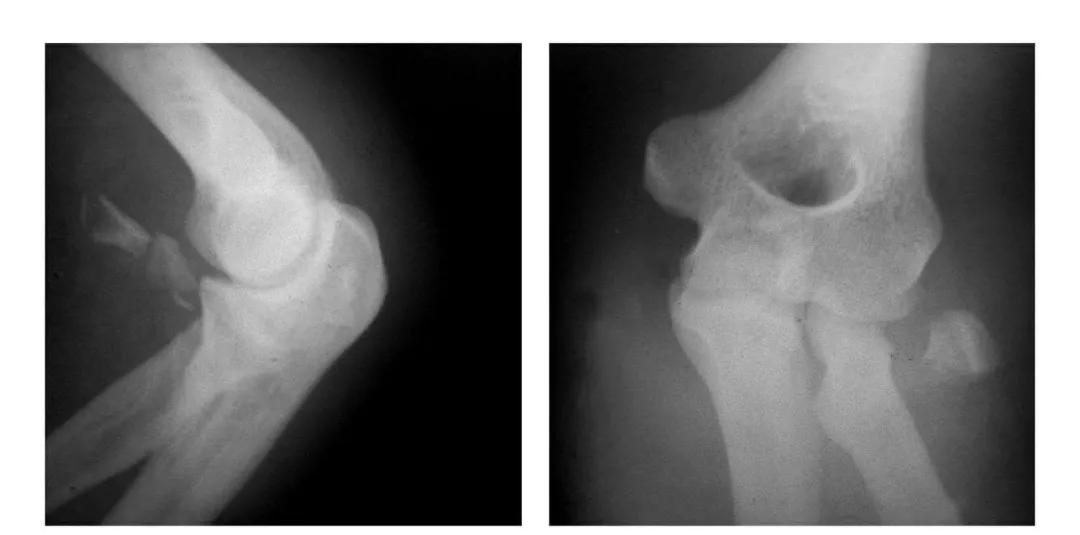

肱骨小头冠状面骨折

(一)完全骨折

本病亦称哈-斯(Hahn-Steinthal)型骨折

例1:肱骨小头基底部呈冠状面骨折,骨折块呈半球状向肘前上方移位。

例2:肱骨小头基底部冠状面骨折,骨折块呈半球状向肘前移位并肱骨内上髁无移位骨折。

(二)部分骨折

本病亦称科-洛(Kocher-Lorenz)型骨折

例1:肱骨小头软骨面及其下方少量骨质呈“新月样”被剥脱,且向肘前上方移位并桡骨头前半部骨折。

例2:肱骨小头软骨面剥脱性骨折,致该小头新月状骨片被向前脱位的桡骨头顶向肘关节前上方,并尺骨干中段骨折(孟氏伸展型骨折)。